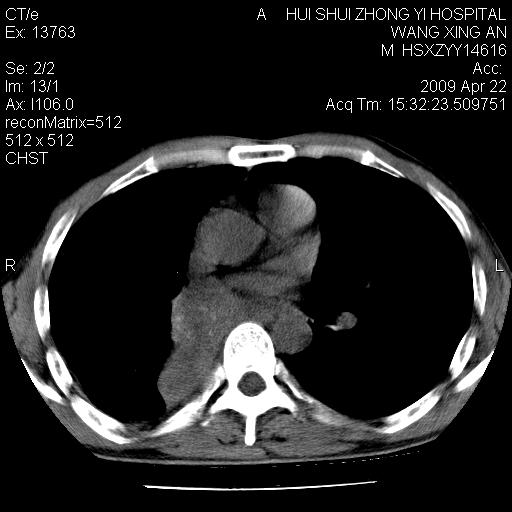

标题: CT19534:患者男、46岁咳嗽、胸痛半月。 [打印本页]

标题: CT19534:患者男、46岁咳嗽、胸痛半月。

支持右侧中央型肺ca并右下肺不张、右侧胸腔少量积液。

1、右下肺中央型肺癌并右肺转移,右肺下叶不张。(右肺有结节影)。

2、右中上肺陈旧性肺结核(因为大多为纤维灶)。

3、右侧胸腔积液。

右侧中心性肺癌并下叶肺不张,双肺及纵隔淋巴结转移,右侧胸腔积液

1、右下肺中央型肺癌并右肺转移,右肺下叶不张。(肿块围绕右肺下叶支气管生长,致管腔闭塞右肺下叶不张;右肺有结节影)。

2、右侧胸腔积液。

3、右中上肺陈旧性肺结核(右肺见纤维化病灶及点状钙化)。

1。右下肺中央型肺癌并肺转移,右肺下叶不张。(两肺都有结节影)。

1)右肺中间段支气管癌并右肺下叶肺不张。2)右肺上叶、两肺下叶背段感染性病变。3)右侧少量胸腔积液。